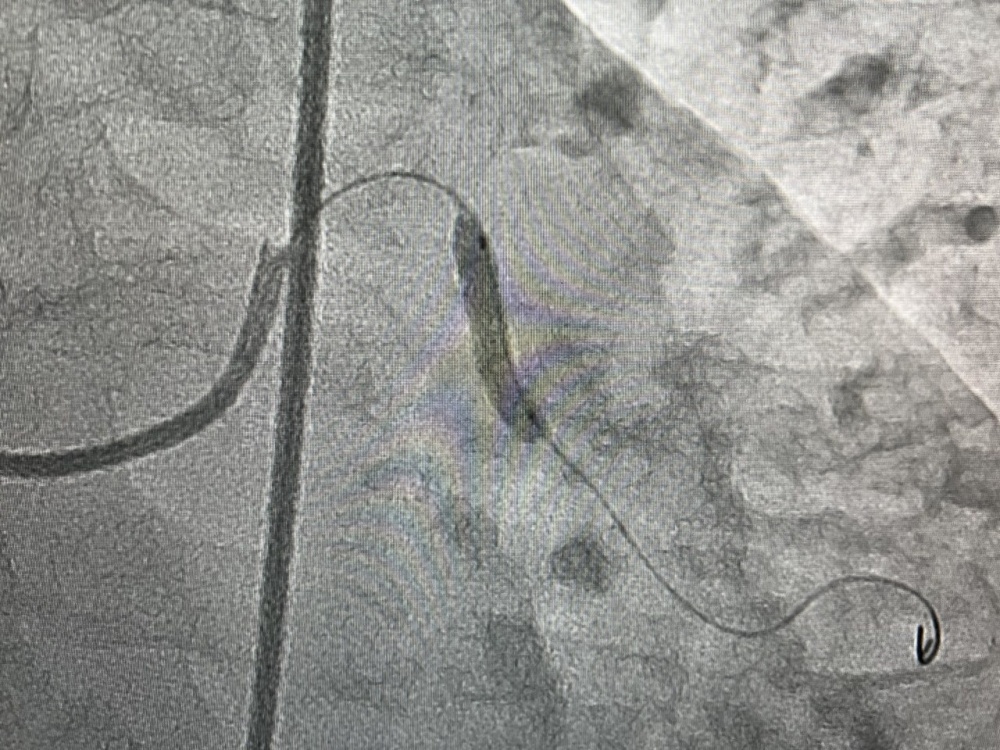

В отделение рентгенохирургии Южного регионального научного центра сердечно-сосудистой хирургии в Жалал-Абаде уже с марта привозят больных с различными сердечными патологиями, в том числе с острым коронарным синдромом из сел и райцентров Жалал-Абадской области. В начале апреля 28 пациентам проведена ангиография, благодаря этому методу контрастного рентгенологического исследования врачи на экране видят чёткое изображение сосудов сердца, их сужения и аномалии. Нескольким из этих больных рентгенохирурги установили стенты, чтобы предотвратить инфаркт миокарда, четверым - уже с острым инфарктом миокарда. Оказана необходимая помощь и пациентам при других формах коронарных синдромов.

На снимках представлено видео стеноза аортального клапана до лечения, в процессе баллонной дилатации и после имплантации и стентирования